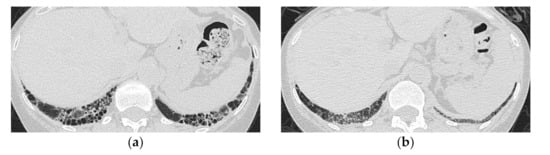

4. HRCT Findings in Relation to the Poorer Prognosis

- Tanizawa, K.; Handa, T.; Nakashima, R.; Kubo, T.; Hosono, Y.; Aihara, K.; Ikezoe, K.; Watanabe, K.; Taguchi, Y.; Hatta, K.; et al. The prognostic value of HRCT in myositis-associated interstitial lung disease. Respir. Med. 2013, 107, 745–752. [Google Scholar] [CrossRef] [PubMed]

- Zou, J.; Guo, Q.; Chi, J.; Wu, H.; Bao, C. HRCT score and serum ferritin level are factors associated to the 1-year mortality of acute interstitial lung disease in clinically amyopathic dermatomyositis patients. Clin. Rheumatol. 2015, 34, 707–714. [Google Scholar] [CrossRef]